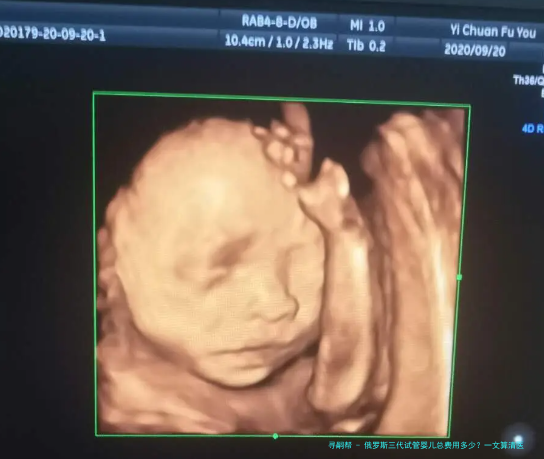

胚胎培育:将取出的卵子和精子在实践室进行体外受精,并培育至囊胚阶段。